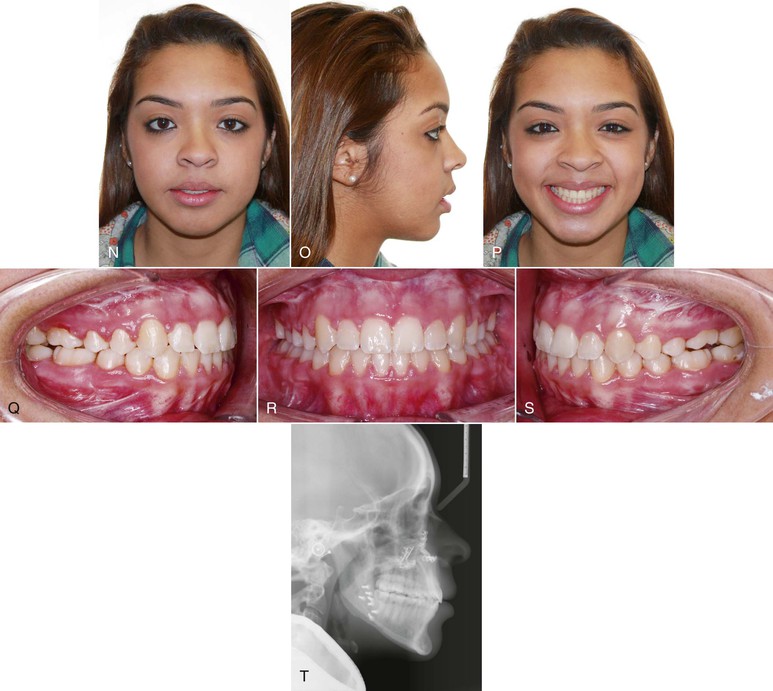

Figure 9-9 Female patient, age 18, with a tongue thrust. A–C, Extraoral views. On smile, only 50% of the incisors are displayed and an anterior tongue posture is evident. A reverse smile arc is consistent with the tongue thrusting habit. D–F, Intraoral views show a 3-mm anterior open bite with divergent occlusal planes from the first premolars. G, Lateral cephalogram shows a dental anterior open bite with dentoalveolar protrusion. H, Habit appliance with first and second molar bands and anterior loop design close to the palate. I, Intraoral view of the cemented habit appliance. J, Brackets are placed after 6 months of exclusive treatment with the habit appliance. Fifty percent of the negative open bite self-corrected. K–M, Extraoral views after treatment. A positive smile arc was obtained, with approximately 90% incisor show on smile. N–P, Adequate overbite was achieved with a good Class I relationship. Q, Final lateral cephalogram shows the overbite correction. R, General superimposition shows no maxillary or mandibular growth. Controlled lingual tipping of the upper and lower incisors reduced the dentoalveolar protrusion and anterior open bite. S, Regional maxillary and mandibular superimpositions show the same dental movements described previously (pre-treatment age, 18.8 years; post-treatment age, 21.5 years).